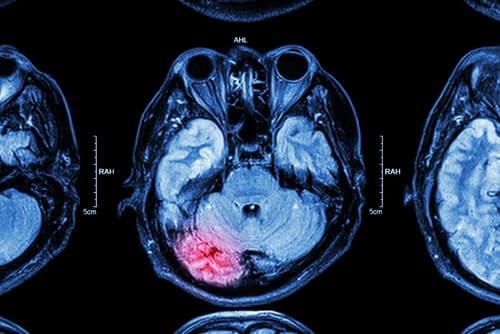

A traumatic brain injury is usually the result of a forceful blow or strike to the head. It may occur if your head comes into contact with an object, like if your head hits the dashboard during a car accident. A TBI can also occur if a falling object hits your head, like a piece of scaffolding that falls from a construction site.

If the head trauma does not involve penetration of the skull, it is known as a closed head injury. In contrast, an open head injury, or penetrating trauma, is more likely to cause brain damage since it pierces through the skull and directly into brain tissue.